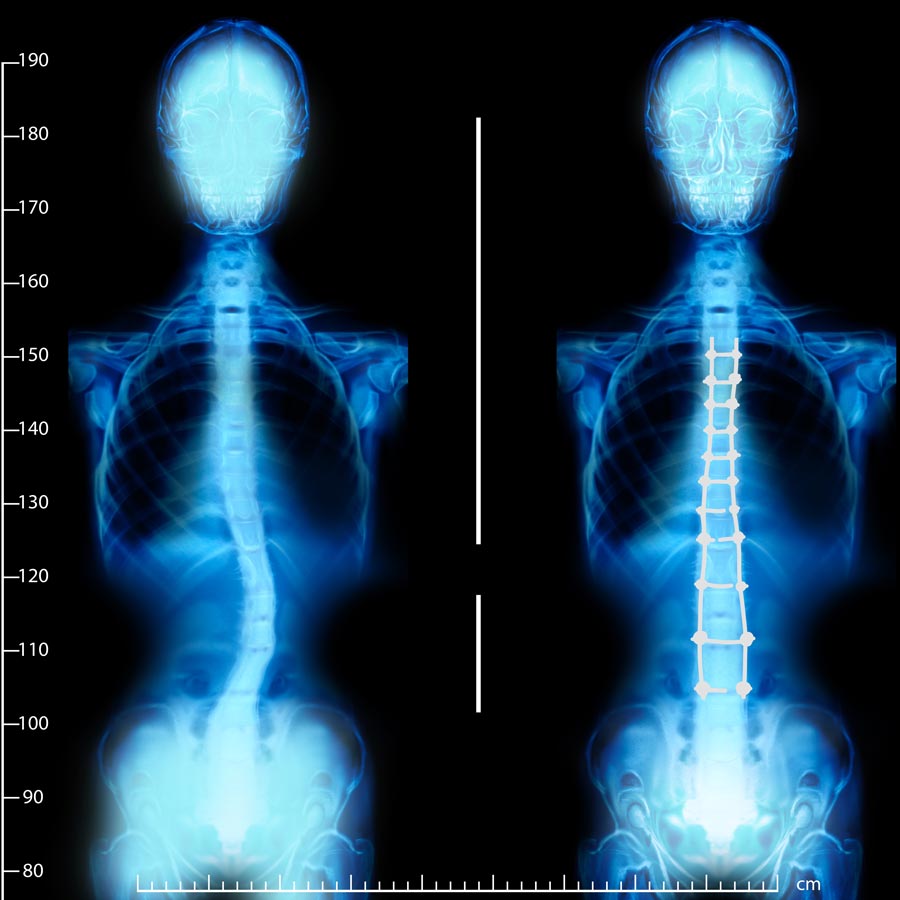

Scoliosis is more than just a sideways curve in the spine – it can impact everything from posture and balance to breathing capacity, mobility, and self-confidence. Whether it was identified during adolescence or has gradually developed in adulthood, scoliosis often causes compensations that strain muscles, irritate nerves, and lead to long-term dysfunction if left unaddressed.

At Hood Chiropractic, scoliosis care starts with clarity. Dr. Chris and his team perform a detailed exam including digital posture analysis, full-spine X-rays, and structural assessments to identify the type and severity of scoliosis. From there, we build a customized treatment plan designed to stabilize, reduce, or even reverse the curve – depending on your unique case.

Treatment may include mirror-image spinal adjustments, corrective traction, neuromuscular re-education, and guided exercises. As a Chiropractic BioPhysics® provider, Dr. Chris uses techniques that go beyond traditional chiropractic to target spinal structure and long-term function.